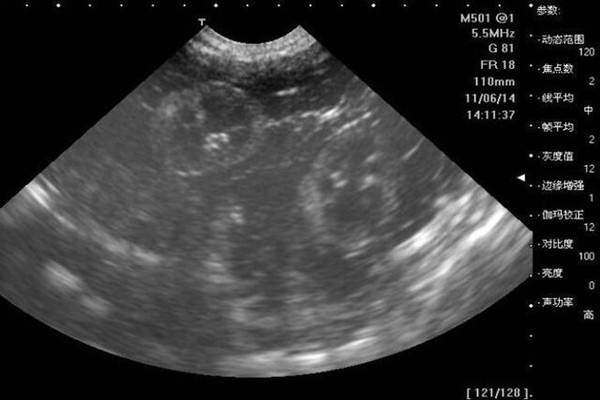

B超单10秒测出怀男孩和女孩

一、看孕早期B超单测男女1、看B超数据:如果孕囊长和宽的相差在一倍以上,男宝宝可能性大。孕囊的长和宽相等,女宝宝可能性大。2、看孕囊形状:像茄子或长条状的是男宝宝可能性大,圆圆的是女宝宝的可能性大。

二、看孕后期B超单测男女。孕后期B超单中,双顶径减去股骨长的值大于2,男宝宝可能性大,值小于2,女宝宝可能性大。